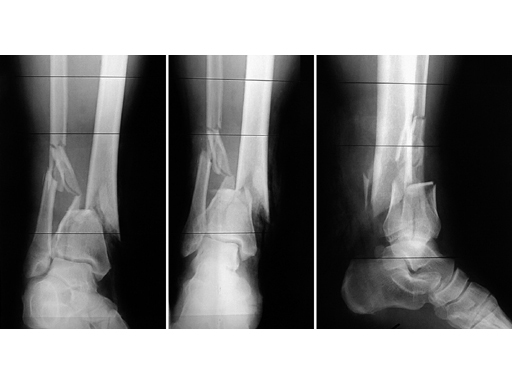

51-year-old man